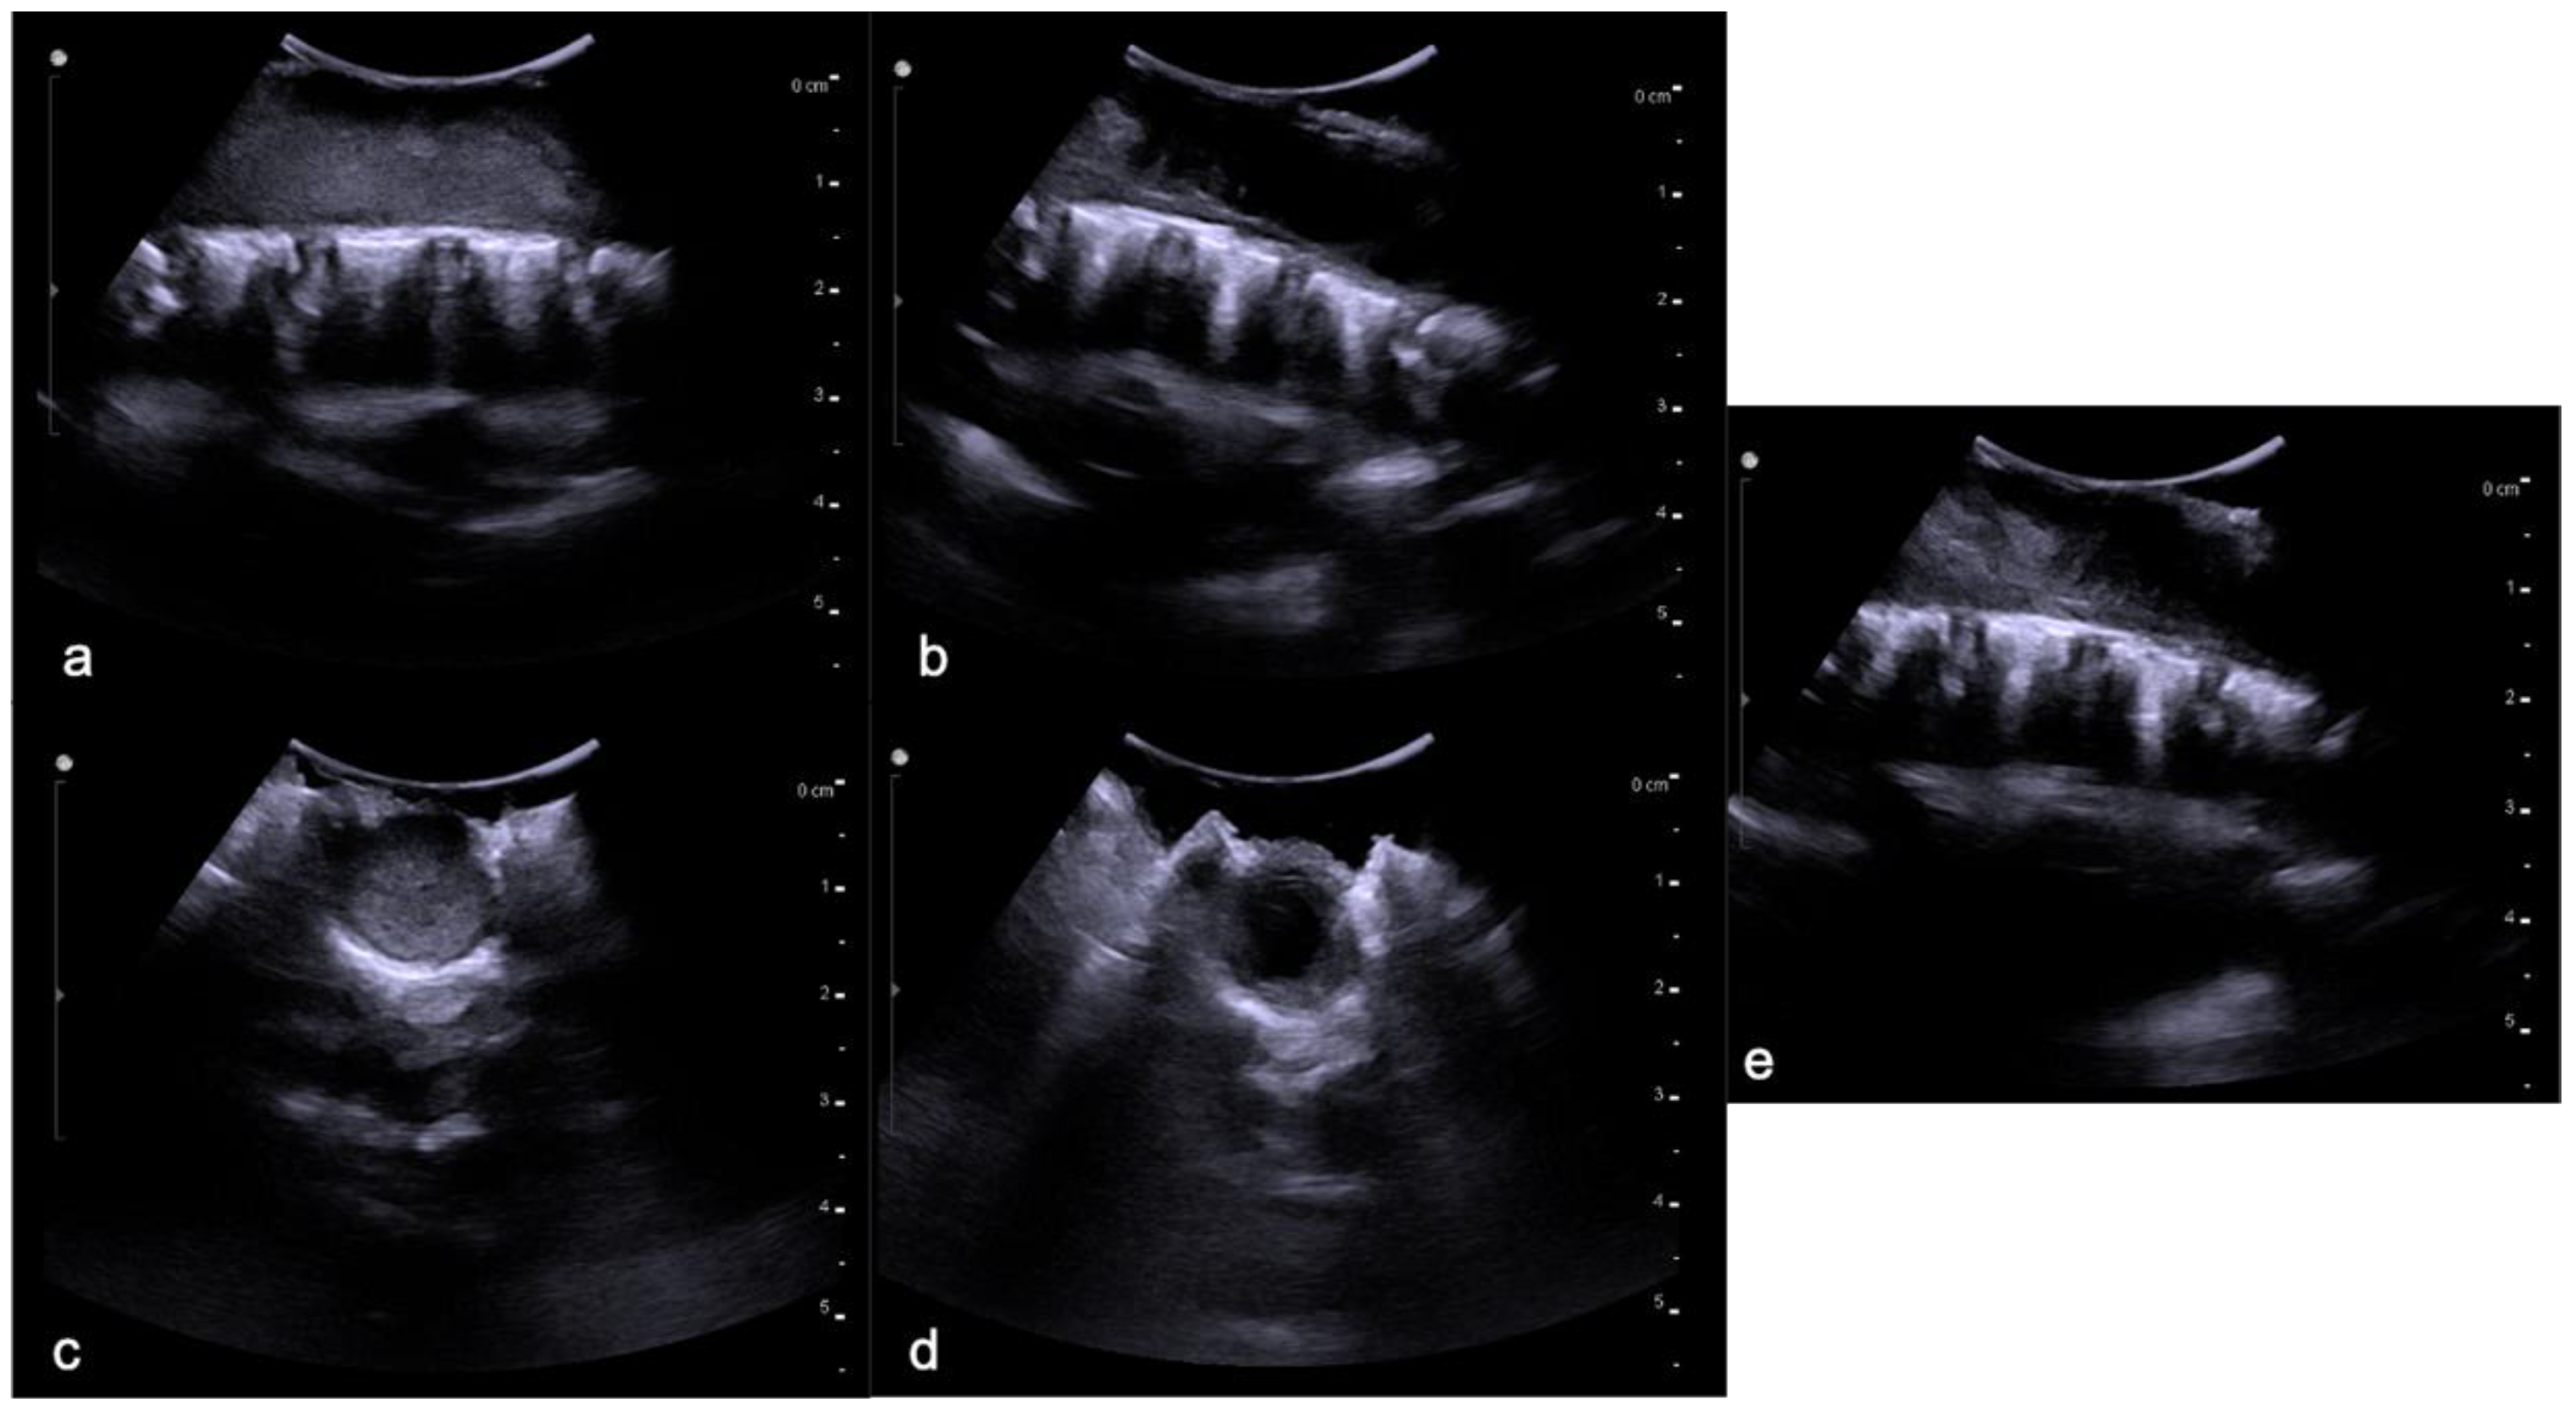

Figure 9.

Hemangioblastomas in a fifteen-year-old child with cystic solid components located in the cervical–dorsal junction. Sagittal T2-weighted (a) and post-contrast T1-weighted (b) images demonstrate the enhancing solid nodular components (arrows) and the cystic component (arrowhead). After two years (c,d), the cystic component increased while the solid component remained stable.